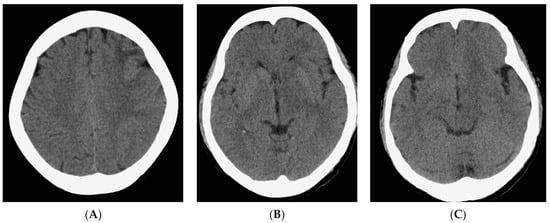

Upon evaluation, her fever persisted at 38.2 degrees Celsius, and laboratory investigations revealed leukopenia with a white blood cell count (WBC) of 610/μL. The urinalysis showed no evidence of pyuria, and the chest X-ray results were unremarkable. The treatment included the administration of Granulocyte Colony-Stimulating Factor (GCSF) for leukopenia and empirical antibiotics, specifically piperacillin/tazobactam, to address the neutropenic fever. An extensive infectious workup was conducted on admission, including a cerebrospinal fluid (CSF) analysis, which did not identify a clear infectious focus. The blood cultures yielded no bacterial growth. The patient’s WBC count elevated to 7430/μL after GCSF treatment. However, intermittent fever was still observed. Six days after admission, she exhibited a slow response and developed right-sided weakness. A relapse of CNS lymphoma or other CNS lesion was suspected. A brain computed tomography (CT) scan revealed abnormal hypointense changes in the left frontal lobe, left basal ganglion, left thalamus, and left cerebral peduncle with associated brain swelling (Figure 1). The subsequent magnetic resonance imaging (MRI), performed three days later, revealed hyperintensity in the left frontal and left parietal lobes, bilateral corona radiata, basal ganglia, and thalami, as well as the left temporal lobe and left-side brainstem on T2 weighted images (T2WIs), fluid attenuated inversion recovery (FLAIR), and diffusion weighted images (DWIs) without obvious restricted diffusion. No definite contrast enhancement was observed on the post-gadolinium T1 weighted images (Gd-T1WIs) (Figure 2). The presence of a mass effect from the infiltrative lesions, resulting in the compression of the left lateral ventricle and a midline shift to the right side, was observed. Notably, magnetic resonance spectroscopy (MRS) focused on the left basal ganglion lesion showed an elevated choline peak and decreased N-acetylaspartate (NAA) peak, with the presence of a lactate peak (Figure 3). A stereotactic brain biopsy for the left basal ganglion lesion and the left frontal lobe lesion confirmed the presence of diffuse large B-cell lymphoma, and the patient subsequently received whole-brain radiotherapy. Following treatment, the patient’s consciousness improved to an alert state (E4V5M6), and her right limb muscle strength showed improvement. Under stable conditions, she underwent another cycle of R-CHOP chemotherapy and completed whole-brain radiotherapy (WBRT). The patient was transferred to a nursing home under a stable clinical condition.

Figure 1. Non-contrast CT scan of brain. The images show a hypointense area with brain swelling at left frontal lobe (A), left basal ganglion (B), left thalamus (B) and left cerebral peduncle (C).